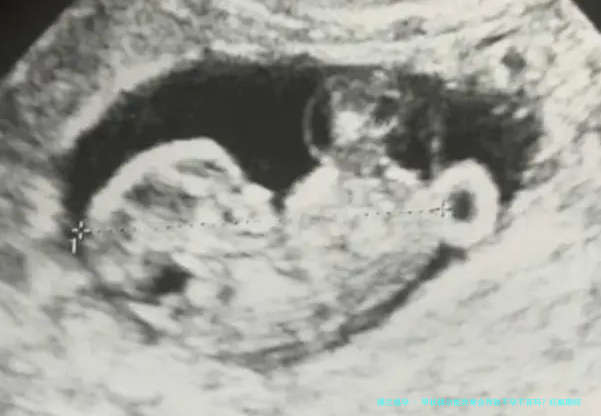

怀孕期间,甲状腺功能的正常是否对母婴健康极为重要。甲状腺激素不但影响母亲的革故鼎新,还对胎儿的大脑和骨骼发育起到重要作用。所以,孕期须要重点关注甲状腺功能的变迁,并保证那个地方于适合范畴内。